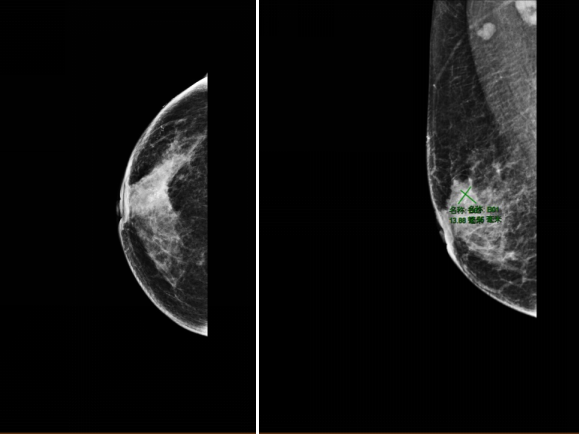

2021-12-01,乳腺MR:右乳外上象限腺体内(约9-12点钟方向,前中带区)见一异常信号肿块影,大小约3.9×2.7cm,符合乳腺癌表现(BI-RADS 6类),侵及邻近皮肤及乳头。右侧腋窝数个增大及稍大淋巴结,较大者大小约为2.1×1.3cm,考虑转移。

图2.乳腺MR(2021-12-01)

2022-4-19,乳腺MR:右乳外上象限腺体内(约9-12点钟方向,前中带区)条片影,大小约2.5×0.7cm,较前明显缩小、强化减低。右侧腋窝数个小淋巴结,较大者短径约0.5cm,较前缩小。

图5.乳腺MR(2022-4-19)